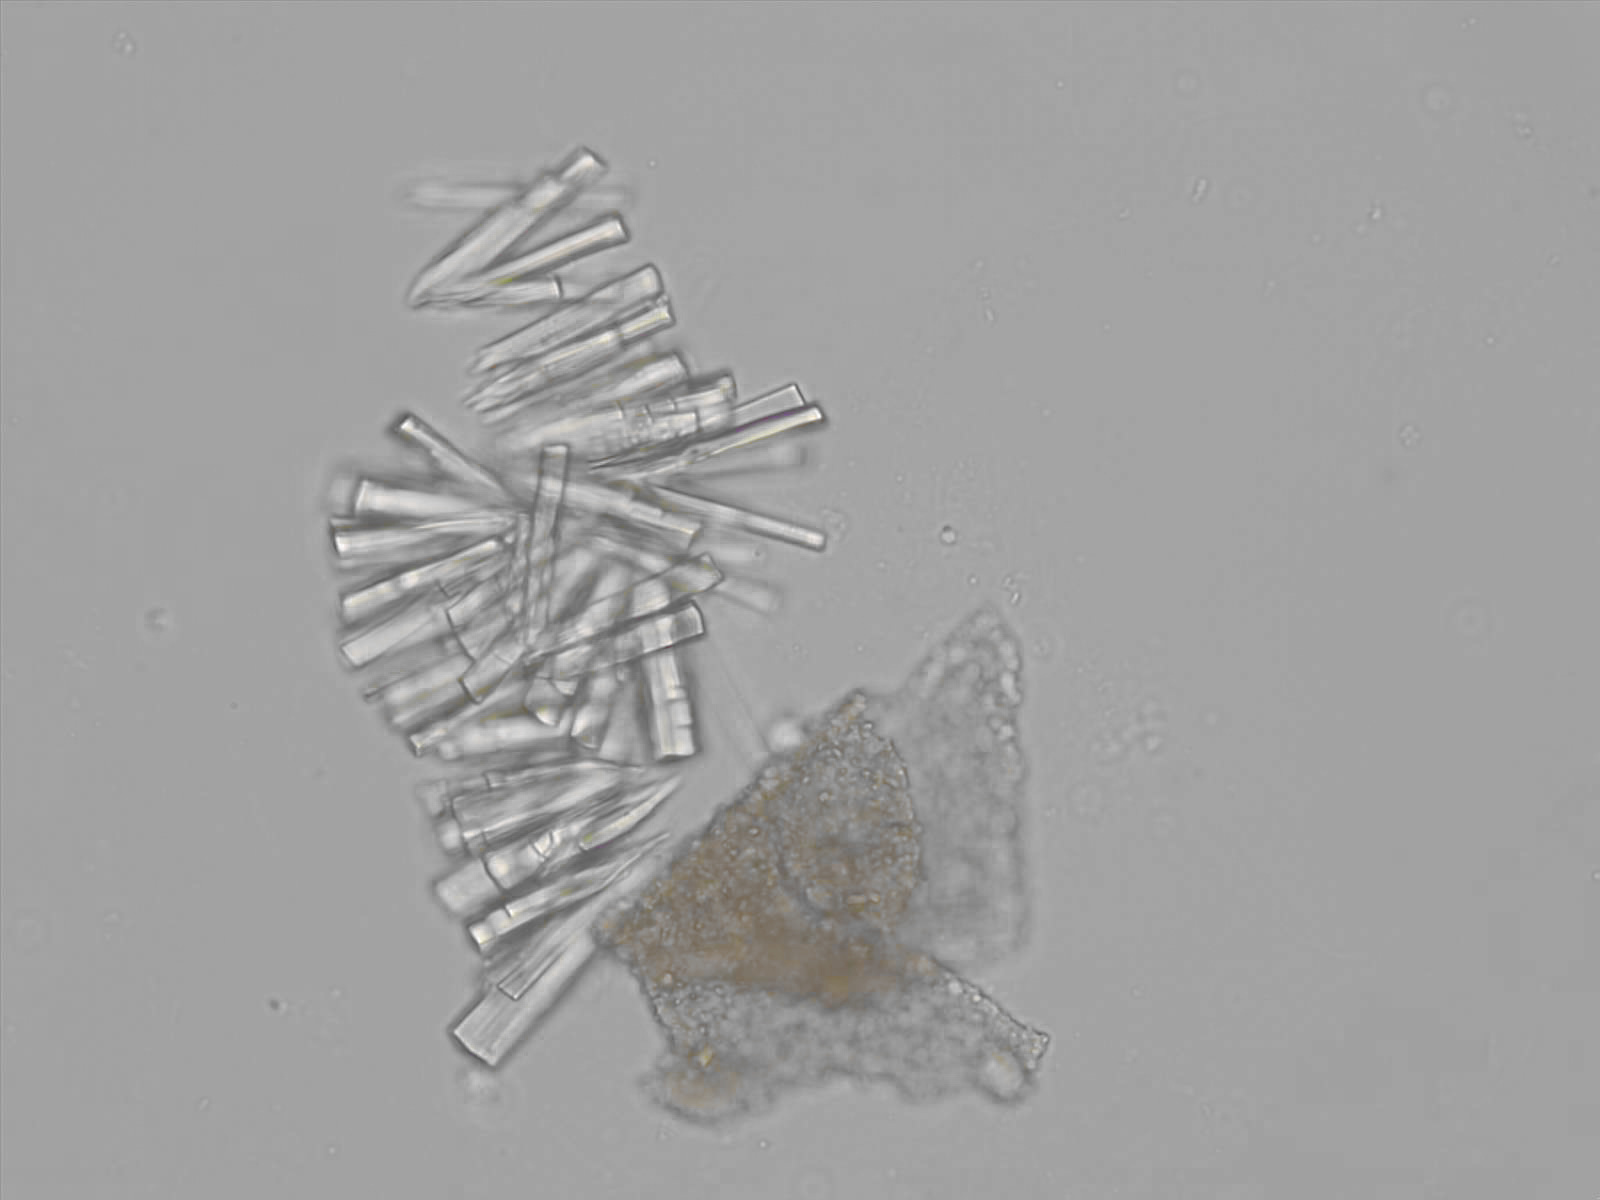

Calcium phosphate - Wedge form

Synonyms: Brushite, CaHPO₄·2H₂O

Calcium phosphate crystals frequently occur in normal urine with an alkaline pH (>7.0), but are also seen in people who form kidney stones. They are colorless and show great morphological variation. The crystals may occur as prismatic shapes, needle or wedge-shaped rods with usually blunt ends, and sometimes as star-shaped clusters (rosettes). These shapes are usually strongly birefringent. In addition, large, flat plates with irregular edges and granular structure can also be found. However, these plates are not birefringent.

Wedge-shaped calcium phosphate crystals may resemble crystals of uric acid, but the distinction can be made on the basis of the urinary pH (acidic in uric acid, basic in calcium phosphate) and the optical behavior under polarized light: uric acid crystals are birefringent, calcium phosphate sheets usually are not.